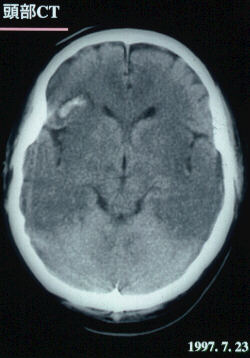

頭部CTスキャン

ところが、左前頭葉に脳出血が起きた。